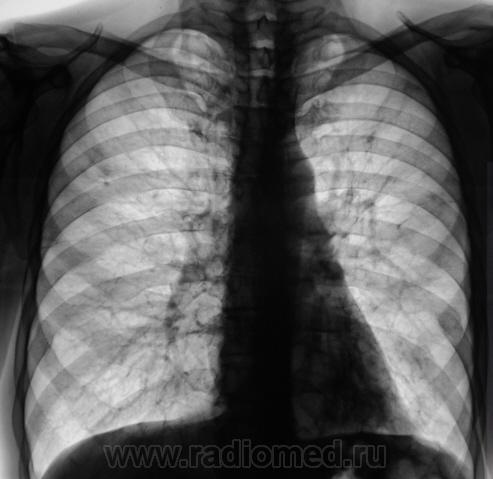

Мужчина; за 50 лет; любитель выпить и подебоширить; двусторонний очаговый туберкулез.....

Да, Виктор Григорьевич.

Отправили к фтизиатрам, те не упирались, только сказали, что слава Богу, хоть не инфильтративный.